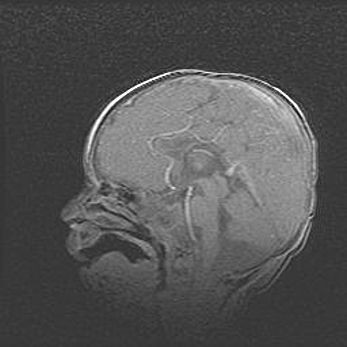

Мальформация Денди-Уокера. Киста задней черепной ямки.

Агенезия мозолистого тела.

Возраст: 2,5 месяца

Вес: 2420 г

Пол: женский

Окружность головы: 37 см

Срок гестации: 32 недели

Мальформация Денди—Уокера — редкий вид патологии ЦНС, представляющий собой врожденный порок развития каудального отдела ствола и червя мозжечка, ведущий к неполному раскрытию срединной (Мажанди) и латеральных (Лушка) апертур IV желудочка мозга. Для этогно синдрома характерна триада симптомов: гипотрофия червя мозжечка и/или полушарий мозжечка, кисты задней черепной ямки, гидроцефалия различной степени. В 70% случаев порок сочетается и с другими аномалиями головного мозга, в частности с агенезией мозолистого тела.